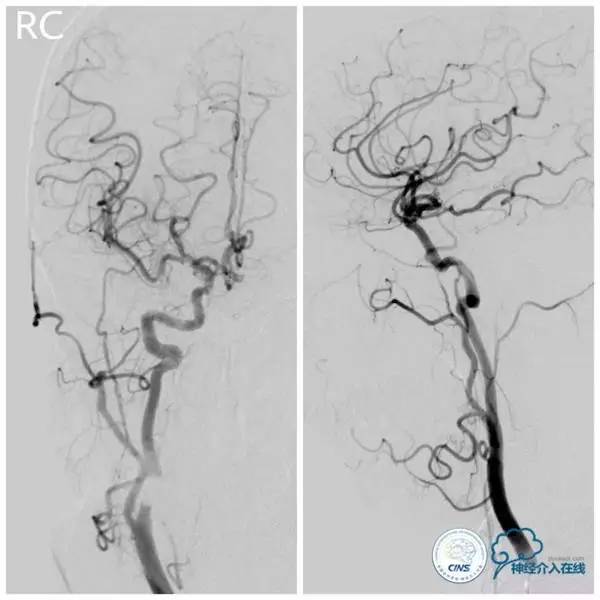

全麻下右侧股动脉穿刺置入6F动脉鞘,交换置入7F长鞘(70cm)置于左锁骨下动脉近端,沿长鞘送入6F Navien导管(115cm)置于左椎动脉V2段以远,造影示基底动脉近段重度狭窄(图7)。

图7

Pilot微导丝(0.014”,190cm)路径图下谨慎通过基底动脉近端狭窄段至左小脑前下动脉,沿微导丝送入Ultra-soft (2.0×20mm)球囊至基底动脉近端狭窄段预扩张(图8)。

图8